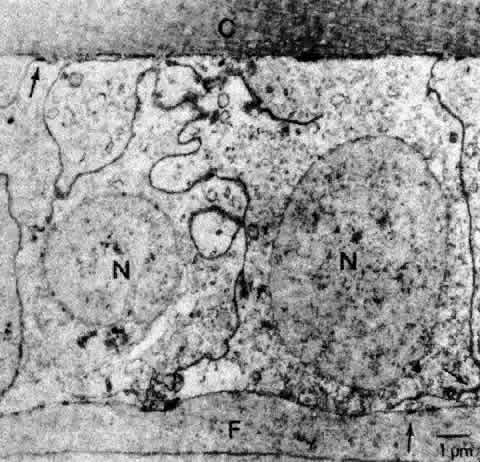

Unlike the cells of the central zone, the germinative zone cells, located peripherally on a whole-mount preparation, actively divide (see Fig. 15). In sagittal section (see Fig. 15), where they are located pre-equatorially, the cells are smaller and more cuboidal and contain more mitochondria than cells of the central zone.84 The cells are joined by a large number of lateral interdigitations (Fig. 16).

Fig. 16. A transmission electron micrograph of cells near the germinative zone of an adult human lens epithelium. The cells contain a number of organelles typical of epithelia. The lateral borders between the cells are highly convoluted and are marked by numerous desmosomes (arrows) and junctional complexes located near the apices. C, capsule; F, fiber; N, nucleus.